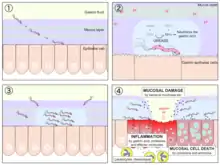

The first step in bacterial infection is colonization of bacteria in host cell aided by adherence factors. In general, adherence to a host cell depends on a eukaryotic acceptor and a bacterial ligand. The eukaryotic acceptor is usually a carbohydrate or peptide residue on the membrane surface while the bacterial ligand, or adhesin, is a macromolecular component of the cell surface that interacts with the receptor. A common adhesin is the fimbrae, which are proteins filaments on the bacterial surface. A bacterial cell will first approach the host cell in nonspecific adherence, which includes possible hydrophobic interactions and electrostatic attractions. This is the docking phase of the bacterial cell leading to specific adherence, which involves permanent formation of bonds between the bacteria and host cells that are mostly irreversible under physiological conditions.

After colonizing a host cell, bacteria will utilize invasion factors to break down the host’s defenses. These substances are termed invasins and act in short distances to break down primary and secondary cell defenses. Many bacteria are also surrounded by capsules that protect them from phagocytosis or opsonization. Spreading factors affect the physical properties of tissues and intercellular components of cells helping to spread the bacteria. Hyaluronidase is in enzyme that attacks the connective tissue by depolymerizing hyaluronic acid. Collagenase breaks down collagen, which is a major building material for muscles and tissue. Neuraminidase breaks down sialic acid, which gives structure to the epithelial cells in the intestines.